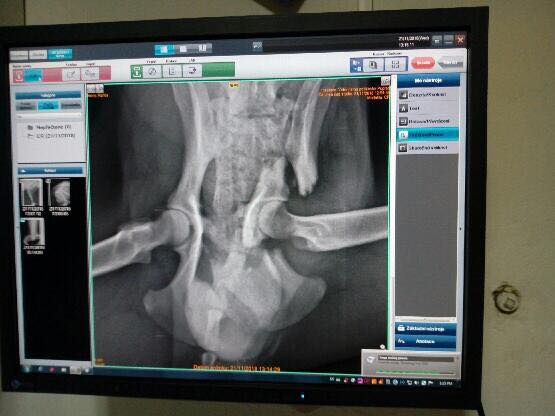

KARLOS, pes, narodený v decembri 2017, cca 45 cm. Nádherný Karlos sa našiel v Smižanoch, kde sa potuloval niekoľko dní a ťahal za sebou nožičku. Nevieme presne, čo sa mu stalo, pravdepodobne išlo o zrážku s autom, ale zlomenina panvy bola veľmi komplikovaná. Vďaka šikovným veterinárom na klinike SIBRA v Bratislave sa však Karlos opäť postavil na nohy.